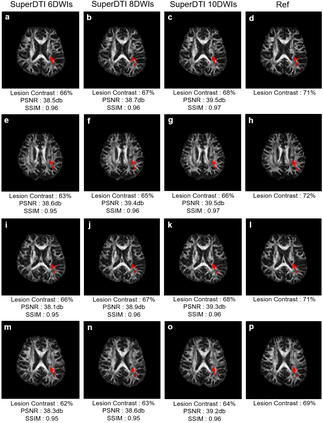

Purpose: To propose a deep learning-based reconstruction framework for ultrafast and robust diffusion tensor imaging and fiber tractography. Methods: We propose SuperDTI to learn the nonlinear relationship between diffusion-weighted images (DWIs) and the corresponding tensor-derived quantitative maps as well as the fiber tractography. Super DTI bypasses the tensor fitting procedure, which is well known to be highly susceptible to noise and motion in DWIs. The network is trained and tested using datasets from Human Connectome Project and patients with ischemic stroke. SuperDTI is compared against the state-of-the-art methods for diffusion map reconstruction and fiber tracking. Results: Using training and testing data both from the same protocol and scanner, SuperDTI is shown to generate fractional anisotropy and mean diffusivity maps, as well as fiber tractography, from as few as six raw DWIs. The method achieves a quantification error of less than 5% in all regions of interest in white matter and gray matter structures. We also demonstrate that the trained neural network is robust to noise and motion in the testing data, and the network trained using healthy volunteer data can be directly applied to stroke patient data without compromising the lesion detectability. Conclusion: This paper demonstrates the feasibility of superfast diffusion tensor imaging and fiber tractography using deep learning with as few as six DWIs directly, bypassing tensor fitting. Such a significant reduction in scan time may allow the inclusion of DTI into the clinical routine for many potential applications.